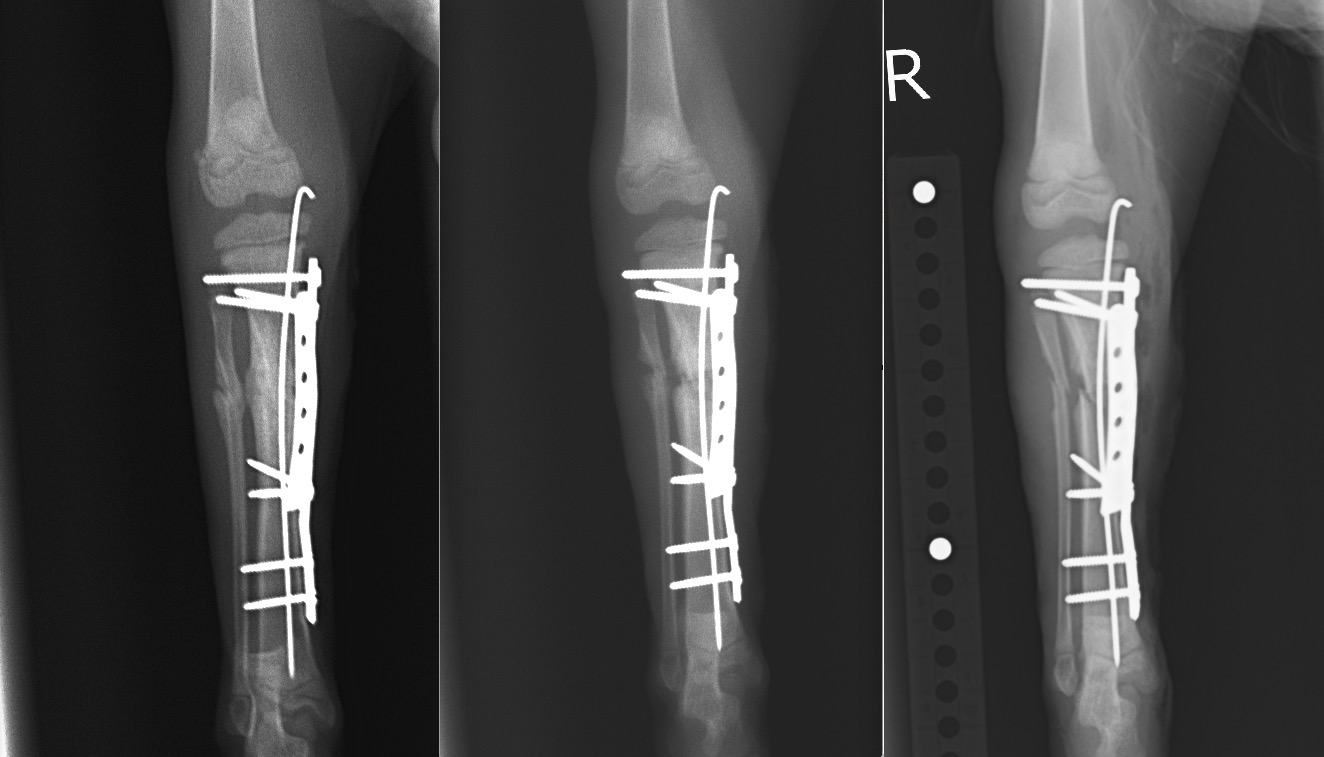

術直後、2週間後、4週間後のX線写真です。

術後4週間/術後2週間/術直後